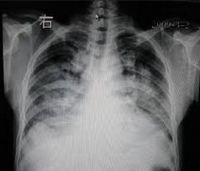

肺水肿间质期的X线表现主要为肺血管纹理模糊,增多,肺门阴影不清,肺透光度降低,肺小叶间隔增宽。两下肺肋膈角区可见与胸膜垂直横向走行的KerleyB线,偶见上肺呈弧形斜向肺门较KerleyB线长的KerleyA线。肺泡水肿主要表现为腺泡状致密阴影,呈不规则相互融合的模糊阴影,弥漫分布或局限于一侧或一叶,或从肺门两侧向外扩展逐渐变淡成典型的蝴蝶状阴影。有时可伴少量胸腔积液。但肺含量增加30%以上才可出现上述表现。CT和核磁共振成像术可定量甚至区分肺充血和肺间质水肿,但费用昂贵。

- 肺泡实变阴影,早期呈结节状阴影,约0.5-1cm大小,边缘模糊,很快融合成斑片或大片状阴影,有含气支气管影像.密度均匀。

- 分布和形态呈多样性,可呈中央型、弥漫型和局限型。中央型表现为两肺中内带对称分布的大片状阴影,肺门区密度较高,形如蝶翼称为蝶翼征。局限型可见于一侧或一叶,多见于右侧。除片状阴影外,还可呈一个或数个较大的圆形阴影,轮廓清楚酷似肿瘤。

- 动态变化:肺水肿最初发生在肺下部、内侧及后部,很快向肺上部、外侧及前部发展,病变常在数小时内有显著变化。

- 胸腔积液:较常见,多为少量积液,呈双侧性。

- 心影增大。